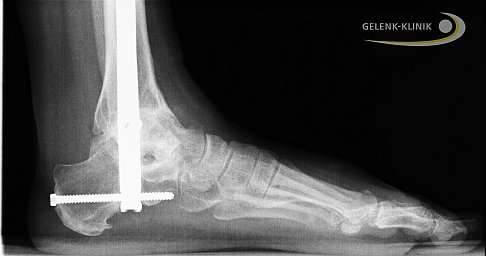

Die Arthrodese des Sprunggelenks kann für viele Patienten wieder schmerzfreie Belastbarkeit herstellen. Die Arthrodese des Sprunggelenks wird mit Schrauben oder Marknägeln durchgeführt, die das Gelenk in fester Position fixieren, bis die Verknöcherung vollständig ist. © Gelenk-Klinik

Die Arthrodese des Sprunggelenks kann auch mit Hilfe eines Marknagels durchgeführt werden, der Schienbein, Sprungbein und Fersenbein stabil verbindet. Vor allem Arthrose des unteren Sprunggelenks und schwere Fehlstellungen des Fersenbeines können diese Methode der Sprunggelenksarthrodese erforderlich machen. Bei dieser Anwendung des Marknagels zur Versteifung des Sprunggelenks wird zusätzlich das Gelenk zwischen Fersenbein und Sprungbein versteift. © Gelenk-Klinik